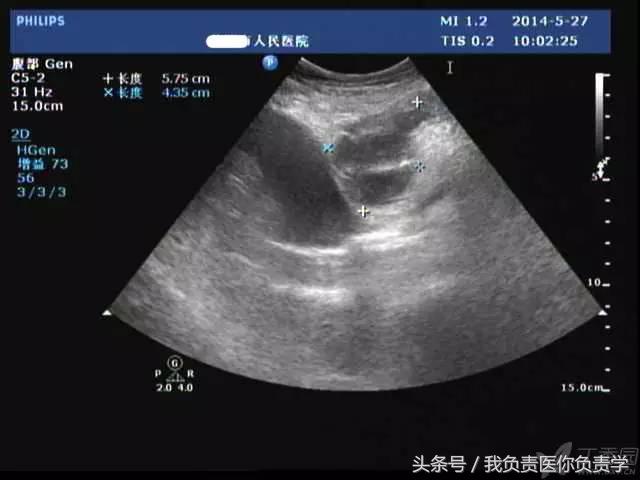

典型病例 5

(由丁香园注册用户「ouchen2010」提供)

患者女,75岁,右上腹疼痛就诊。查体示右上腹压痛明显,无明显腹膜炎体征。

超声检查发现胆囊内可见沉积物及结石回声,胆囊近底部可见 0.5cm 回声中断,十二指肠亦可见 0.5cm 回声中断,二者间见 5.8×4.4cm 混合性团块。

图1示胆囊饱满,内透声差,可见沉积物回声

图2示胆囊、胃窦及十二指肠之间可见混合回声型团块

图3-图5为胆囊局部放大图像,显示胆囊囊壁局部回声中断,周围可见不规则混合回声团块

图6和7为相应CT表现

术后诊断为慢性结石性胆囊炎,胆囊-十二指肠穿孔并内瘘形成。